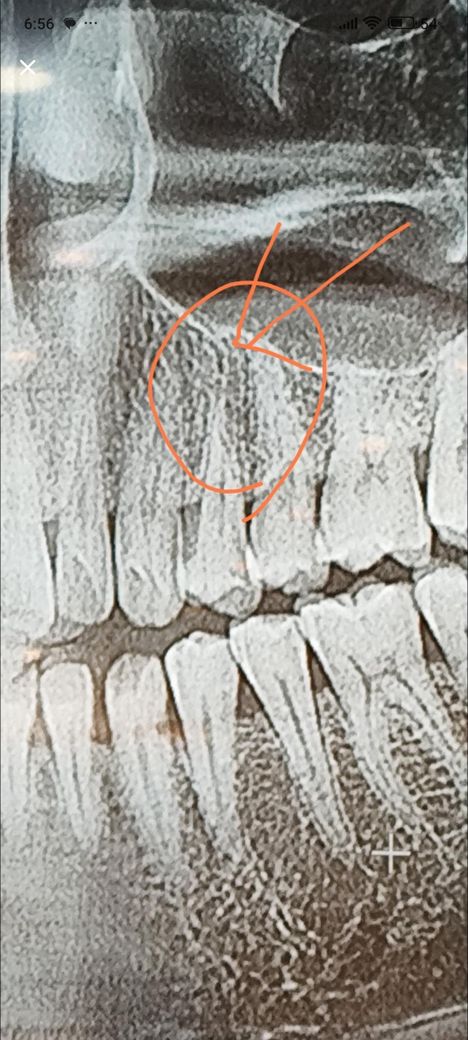

신경치료를 받았는데 게속아픕니다 사진보고 도와주세여

치아가아파 신경치료를 받고 밀봉했는데 게속아프고

두통에 이상감각이들어

재신경치료를 받았는데요 받고 난이후에도 게속 증상이

사라지지않고 감각이상이 게속되고 있어요

두통도오고 머리가 지근거리고

제생각에는 의사가 저화살표부분까지 신경을 제거 안해서

그런증상이 게속되고 있는거 같은데 저검은 실같은 음영부분 신경맞나요?

다른치과가서 더 긴 신경치료기구를 넣어서 치료해달라고 하면 괜찮아 질까요? 사진보시고 판단부탁드려요

사진은 신경치료받기전 사진이에요

사진상에 표시된 부분까지 치아 뿌리가 잇는거 같진 않습니다. 신경치료를 해도 불편하시다면 상악동 염때문에 그럴수도 잇으니 이비인후과도 한번 가보시는게 좋을것같습니다.

1. 위 사진은 파노라마 엑스레이 편집본으로 개별 치아를 보기에 적절하지 않습니다

2. 표시된 위치보단 뿌리가 짧을 것 같습니다

3. 대학치과병원 보존과 가보세요